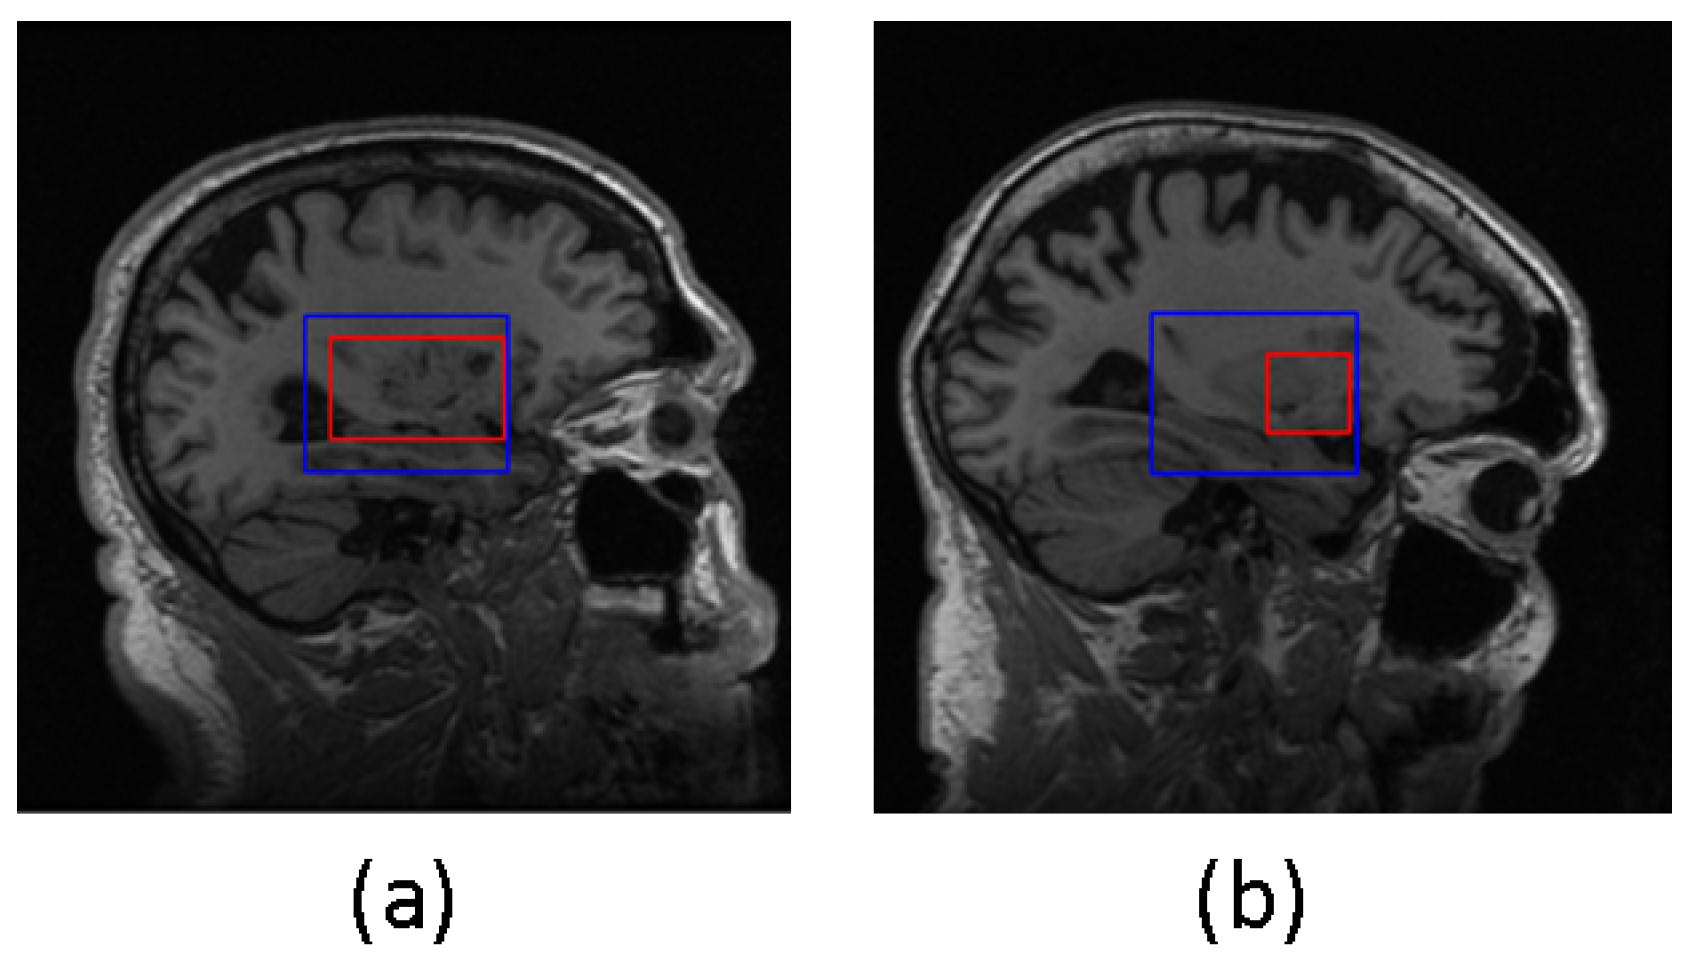

The samples in which the proposed algorithms perform poorly were not excluded from the final classification results. In Figure 5, two examples are presented where the predicted bounding box (shown in blue) accurately encompasses the ground truth hippocampal region (shown in red). In contrast, Figure 6 shows two instances where the agent fails to produce an acceptable bounding box. This issue can be attributed to two factors: firstly, as observed in the example shown in Figure 6a, the hippocampal region was correctly extracted but the agent failed to generate the bounding box that properly encloses the hippocampal region. Secondly, as seen in Figure 6b, the error lies in the accurate representation of the hippocampal ground truth itself.

Figure 5.

Satisfactory localization outcomes from DQN in both examples (a) and (b). Blue box represents the predicted bounding box, and red box represents the truth hippacapus region.